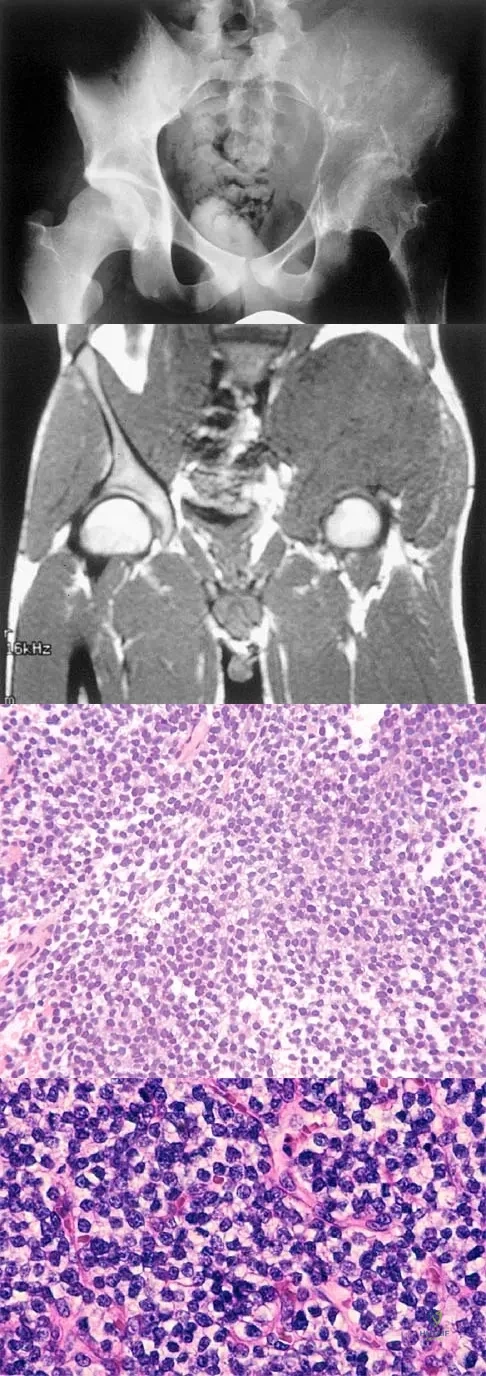

A 16-year-old girl has had hip pain for 1 year. Approximately 2 months ago she noted the development of a hard mass in the right buttock that has steadily increased in size. She now reports severe pain in the right buttock, with radiation down the leg and numbness involving the right foot and toes. A radiograph is shown in Figure 70a and an axial postcontrast T1-weighted MRI scan is shown in Figure 70b. A biopsy specimen is shown in Figure 70c. The chest CT shows multiple lung metastases. Treatment of this lesion should consist of

Explanation